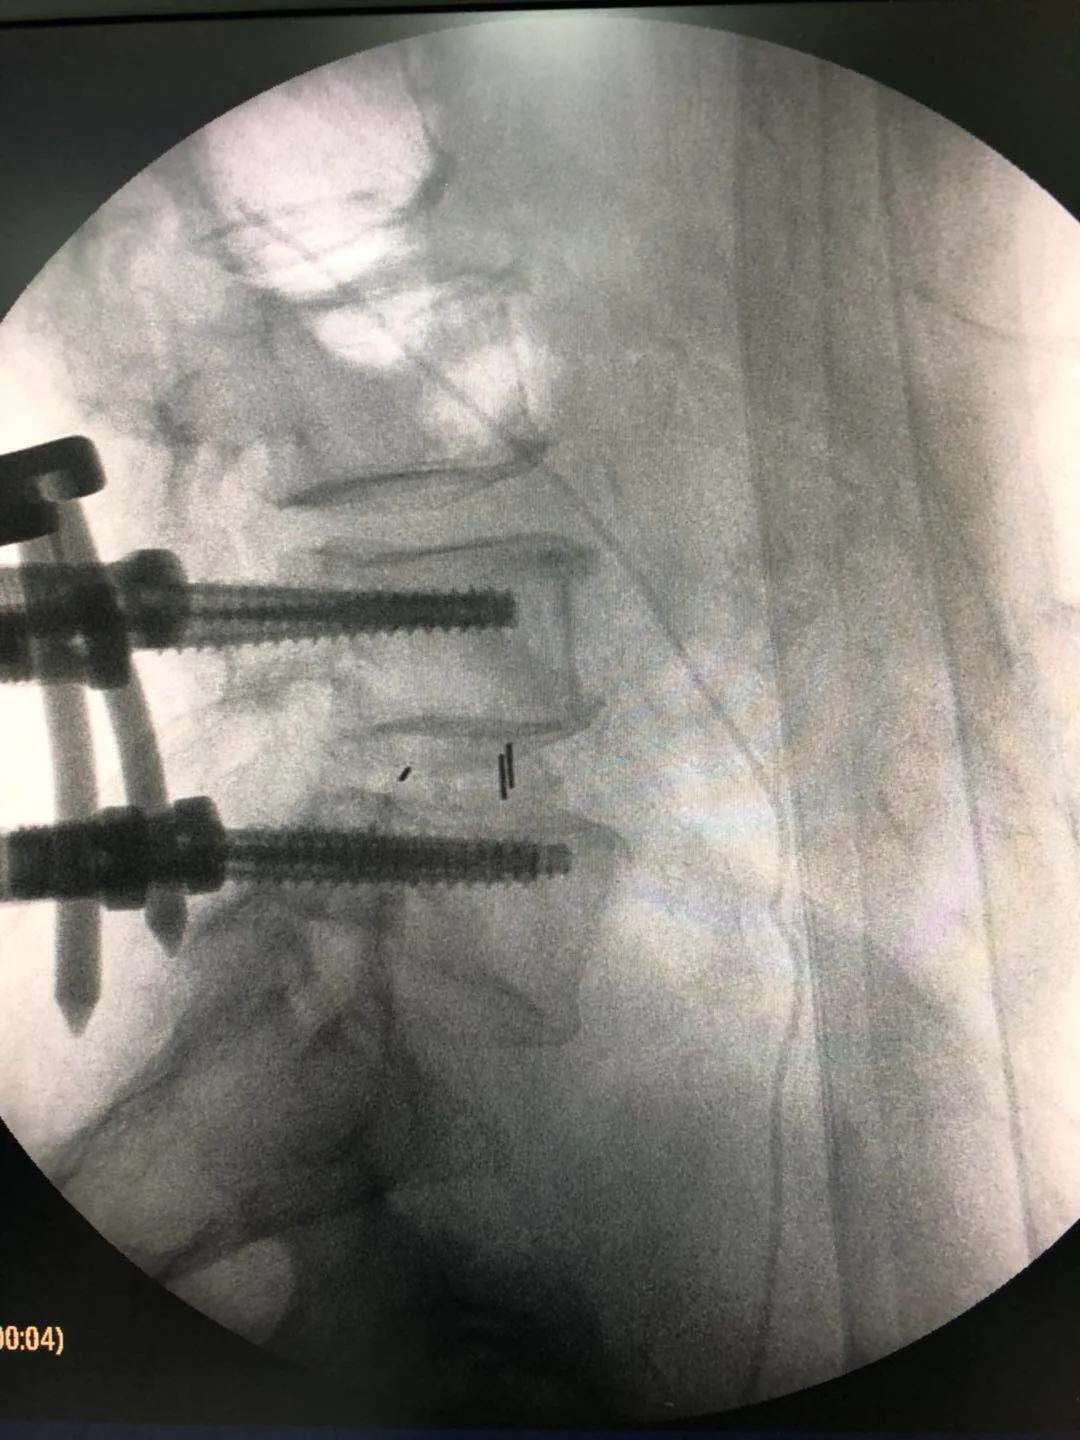

海安市中医院副院长、骨伤科主任魏爱淳主任中医师接诊后,为其制定了UBE(单侧双通道内镜微创技术)治疗方案。做好各项术前准备后,魏爱淳副院长、蒋剑锋主任和他们的手术团队在专家指导下,采用UBE专用综合器械包和专用等离子射频手术系统,成功为患者实施了UBE技术下L3/4椎管减压,L4/5椎管减压、椎间植骨融合术,手术只有5个微创小切口,术后江先生的双下肢疼痛、麻木症状缓解,手术达到预期的效果,获得了患者及家属的一致称赞。

据了解,相比传统的单通道椎间孔镜技术,UBE技术的手术视野和操作空间更广泛,适用于多种类型的腰椎间盘突出症、椎管狭窄症及轻度的腰椎滑脱症,是一项新兴的脊柱微创技术,术中清晰的镜下视野,配合熟练的器械操作,使得椎管减压和椎间融合过程在少剥离、少出血、高效率的条件下顺利完成。